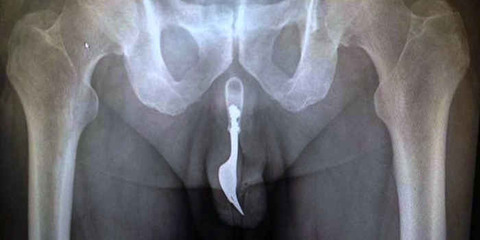

ケツになんか突っ込んで取れなくなった場合と

穴の開いたものにチンコ突っ込んで抜けなくなった場合の対処法は

救急外来の教科書にページを割いて記載されている